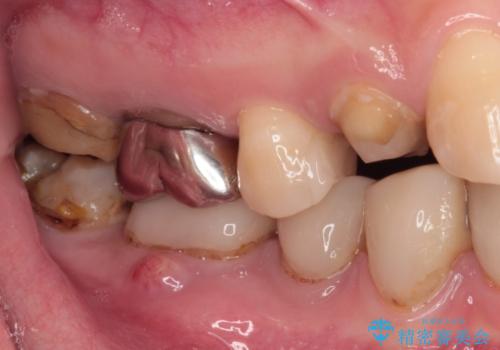

また、奥歯にも痛みがあったり治療途中で放置されていたりと、全顎的な治療が必要な状況でした。

その後、奥歯は痛みのある部分から少しずつ、根管治療やインプラント治療などを行うこととしました。

インプラントが必要となった奥歯は、インプラントが埋入できないほど隣の歯の根尖病変が非常に大きかったため、根管治療を行ったうえで半年ほど待ち、骨が再生したことを確認してからインプラントを埋入しました。期間は長くかかりましたが、大変良い仕上がりとなりました。